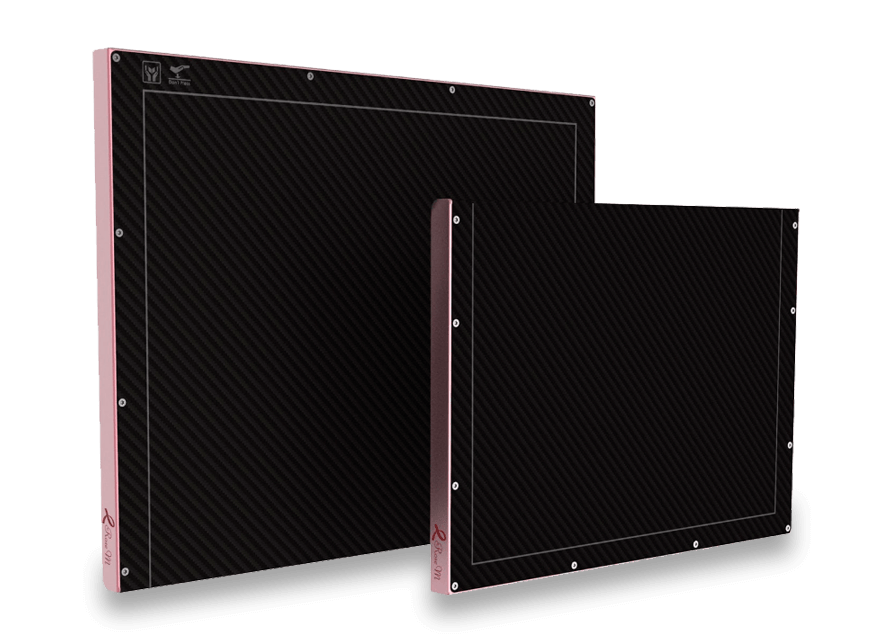

Incorpore la última tecnología en Radiología Digital con nuestra gama de Detectores Flat Panels.

Disponibles para Radiología General, Móvil, Mamografía, Neonatología y Fluoroscopía.

Explore nuestra gama de detectores innovadores y mejore la eficiencia y precisión en sus procedimientos radiológicos.

- Rendimiento superior en sistemas mamográficos.

- El tamaño de píxel más pequeño: 65µm.

- Tecnología a-SE de alta definición.